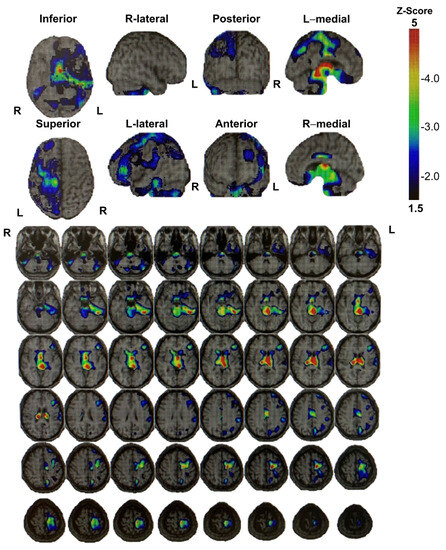

3. Instruments Used for Brain Imaging

4. Discussion and Conclusions

Mechanism Underlying the Pathogenesis